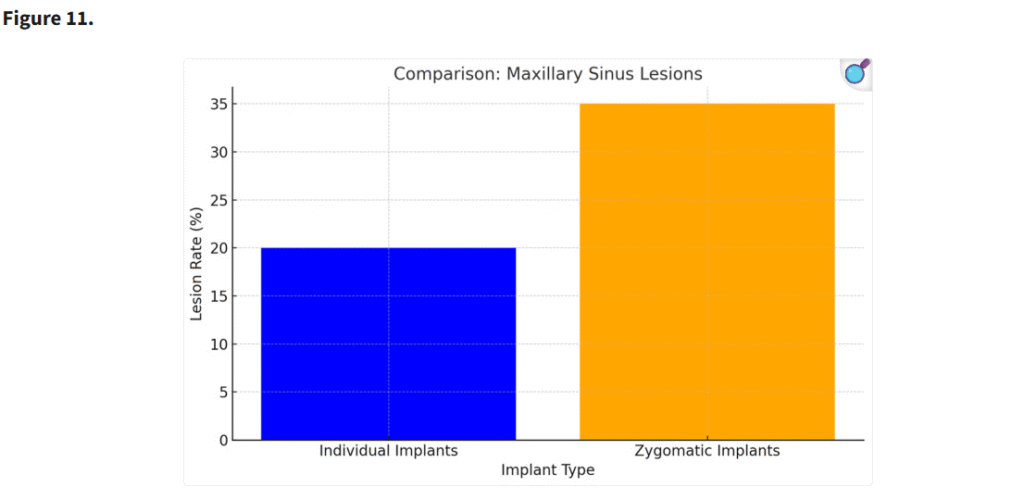

3.3. 上顎洞の術後病変

個別設計インプラントを使用した患者は、ザイゴマインプラントを使用した患者と比較して、術後の上顎洞病変の発生が少なかった(p < 0.05)。個別インプラントの設計と埋入手技により、上顎洞粘膜の穿孔やそれに関連する合併症のリスクが最小限に抑えられた(Figure 11)。

個別インプラントの設計および埋入手技は、上顎洞膜穿孔およびそれに伴う合併症のリスクを最小限に抑えた(p < 0.05)